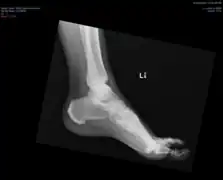

Ectopic calcification and new bone formation in diffuse idiopathic skeletal hyperostosis (DISH)